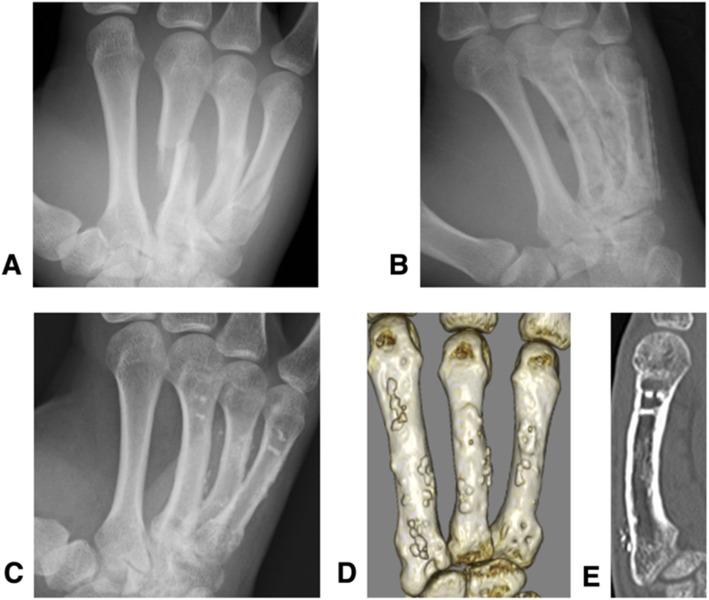

Implants made from bioabsorbable unsintered hydroxyapatite and poly-L-lactate composites (u-HA/PLLA) are widely used in the oral, maxillofacial, and orthopedic fields. This study assess the long-term (> 5 years) outcomes of patients with metacarpal fractures who were surgically treated using bioabsorbable plates and screws (Super-Fixsorb MX40 mesh; Teijin Medical Technology, Osaka, Japan).

A retrospective analysis of six patients with eight metacarpal fractures treated with bioabsorbable plates was done. All patients were followed for more than 5 years post-surgery. The clinical outcomes were evaluated using Q-DASH scores and the grip strength (GS): opposite side ratio. The resorption status of implants was assessed on plain computed tomography (CT) scans at final follow-up appointments.

The mean age of the patients at the time of surgery was 29.5 years (16-54), and the median follow-up period was 81.8 months (68-101). All fractures united without displacement after an average of 3.5 months, and there were no implant specific complications associated with the use of absorbable plates. The mean grip strength ratio was 85.1% (56.8-104.5). The mean Q-DASH scores of 11.36 points (0-34.09) was good in all but two patients. We also observed that it took more than 8 years for the plates to be absorbed completely.

由可吸收的未烧结羟基磷灰石和聚 L-乳酸复合材料(u-HA/PLLA)制成的植入物广泛应用于口腔、颌面和骨科领域。本研究评估了使用可吸收板和螺钉(Super-Fixsorb MX40 网;日本帝人医疗技术公司)治疗掌骨骨折患者的长期(>5 年)结果。

对 6 例 8 处掌骨骨折患者使用可吸收板进行回顾性分析。所有患者术后随访时间均>5 年。使用 Q-DASH 评分和握力(GS):对侧比值评估临床结果。在最后一次随访时,通过平扫 CT 评估植入物的吸收情况。

手术时患者的平均年龄为 29.5 岁(16-54 岁),中位随访时间为 81.8 个月(68-101 个月)。所有骨折在平均 3.5 个月后均无移位愈合,且无与使用可吸收板相关的特定植入物并发症。平均握力比为 85.1%(56.8-104.5)。11.36 分(0-34.09)的平均 Q-DASH 评分在除两名患者外的所有患者中均良好。我们还观察到,板的完全吸收需要超过 8 年的时间。

本研究表明,掌骨骨折的生物吸收过程可能需要 8 年左右完成,并且骨内和骨外的吸收速度不同。可吸收板比金属植入物更具成本效益。可吸收板在各种临床操作中的应用潜力是有希望的。